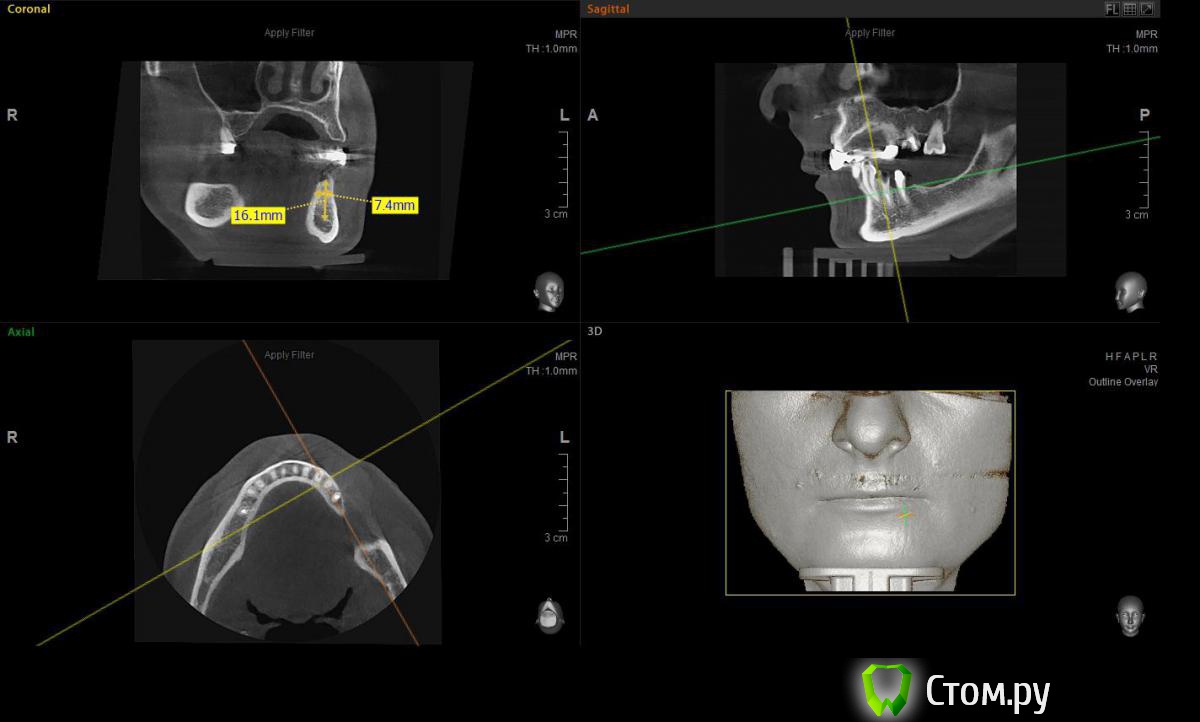

Евгений Ходыкин Опубликовано 2 июля, 2014 Автор Поделиться Опубликовано 2 июля, 2014 Замеры по 3.4 зубу. Срезы с одним замером - это внутрикостная длина корня зуба. Ссылка на комментарий